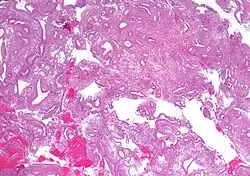

| Micrograph showing simple endometrial hyperplasia, where the gland-to-stroma ratio is preserved but the glands have an irregular shape and/or are dilated. Endometrial biopsy. H&E stain. | |

Endometrial hyperplasia is a condition of excessive proliferation of the cells of the endometrium, or inner lining of the uterus.[1]

Like other hyperplastic disorders, endometrial hyperplasia initially represents a physiological response of endometrial tissue to the growth-promoting actions of estrogen. However, the gland-forming cells of a hyperplastic endometrium may also undergo changes over time which predispose them to cancerous transformation. Several histopathology subtypes of endometrial hyperplasia are recognisable to the pathologist, with different therapeutic and prognostic implications.[4]

- Endometrial hyperplasia (simple or complex) - Irregularity and cystic expansion of glands (simple) or crowding and budding of glands (complex) without worrisome changes in the appearance of individual gland cells. In one study, 1.6% of patients diagnosed with these abnormalities eventually developed endometrial cancer.[7]

- Atypical endometrial hyperplasia (simple or complex) - Simple or complex architectural changes, with worrisome (atypical) changes in gland cells, including cell stratification, tufting, loss of nuclear polarity, enlarged nuclei, and an increase in mitotic activity. These changes are similar to those seen in true cancer cells, but atypical hyperplasia does not show invasion into the connective tissues, the defining characteristic of cancer. The previously mentioned study found that 22% of patients with atypical hyperplasia eventually developed cancer.[7]